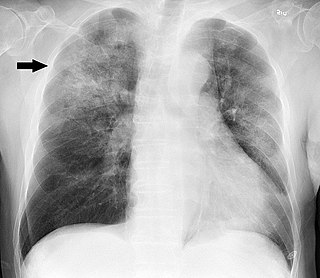

Corticosteroides en la neumonía bacteriana adquirida en la comunidad: una revisión sistemática, metanálisis por pares y dosis-respuesta

La evidencia de certeza moderada indica que los corticosteroides reducen la mortalidad en pacientes con neumonía bacteriana adquirida en la comunidad más grave, la necesidad de ventilación mecánica invasiva y el ingreso en la Unidad de Cuidados Intensivos. J Gen Intern Med 19 de abril de 2023